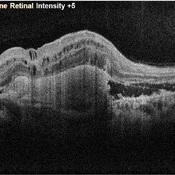

OCT of a Choroidal Neovascular Membrane

Oct 14 2022 by Vaidehi Sathaye

OCT image of a 68 year male patient with a choroidal neovascular membrane in his LE

Photographer: Dr. Vaidehi Sathaye

Imaging device: Mirante

Condition/keywords: CNVM, OCT